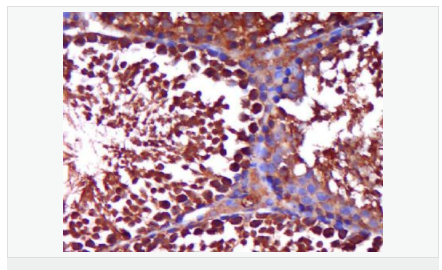

| 產(chǎn)品應(yīng)用 | WB=1:500-2000 ELISA=1:5000-10000 IHC-P=1:100-500 IHC-F=1:100-500 Flow-Cyt=1ug/Test IF=1:100-500 (石蠟切片需做抗原修復(fù)) not yet tested in other applications. optimal dilutions/concentrations should be determined by the end user. |

| 產(chǎn)品介紹 | The androgen receptor gene is more than 90 kb long and codes for a protein that has 3 major functional domains: the N-terminal domain, DNA-binding domain, and androgen-binding domain. The protein functions as a steroid-hormone activated transcription factor. Upon binding the hormone ligand, the receptor dissociates from accessory proteins, translocates into the nucleus, dimerizes, and then stimulates transcription of androgen responsive genes. This gene contains 2 polymorphic trinucleotide repeat segments that encode polyglutamine and polyglycine tracts in the N-terminal transactivation domain of its protein. Expansion of the polyglutamine tract causes spinal bulbar muscular atrophy (Kennedy disease). Mutations in this gene are also associated with complete androgen insensitivity (CAIS). Two alternatively spliced variants encoding distinct isoforms have been described. [provided by RefSeq, Jul 2008] Function: Steroid hormone receptors are ligand-activated transcription factors that regulate eukaryotic gene expression and affect cellular proliferation and differentiation in target tissues. Transcription factor activity is modulated by bound coactivator and corepressor proteins. Transcription activation is down-regulated by NR0B2. Activated, but not phosphorylated, by HIPK3 and ZIPK/DAPK3. [ENZYME REGULATION] AIM-100 (4-amino-5,6-biaryl-furo[2,3-d]pyrimidine) suppresses TNK2-mediated phosphorylation at Tyr-267. Inhibits the binding of the Tyr-267 phosphorylated form to androgen-responsive enhancers (AREs) and its transcriptional activity. Subunit: Binds DNA as a homodimer. Part of a ternary complex containing AR, EFCAB6/DJBP and PARK7. Interacts with HIPK3 and NR0B2 in the presence of androgen. The ligand binding domain interacts with KAT7/HBO1 in the presence of dihydrotestosterone. Interacts with EFCAB6/DJBP, PELP1, PQBP1, RANBP9, RBAK, SPDEF, SRA1, TGFB1I1, ZNF318 and RREB1. Interacts with ZMIZ1/ZIMP10 and ZMIZ2/ZMIP7 which both enhance its transactivation activity. Interacts with SLC30A9 and RAD54L2/ARIP4. Interacts via the ligand-binding domain with LXXLL and FXXLF motifs from NCOA1, NCOA2, NCOA3, NCOA4 and MAGEA11. The AR N-terminal poly-Gln region binds Ran resulting in enhancement of AR-mediated transactivation. Ran-binding decreases as the poly-Gln length increases. Interacts with HIP1 (via coiled coil domain). Interacts (via ligand-binding domain) with TRIM68. Interacts with TNK2. Interacts with USP26. Interacts with RNF6. Interacts (regulated by RNF6 probably through polyubiquitination) with RNF14; regulates AR transcriptional activity. Interacts with PRMT2 and TRIM24. Interacts with GNB2L1/RACK1. Interacts with RANBP10; this interaction enhances dihydrotestosterone-induced AR transcriptional activity. Interacts with PRPF6 in a hormone-independent way; this interaction enhances dihydrotestosterone-induced AR transcriptional activity. Interacts with STK4/MST1. Interacts with ZIPK/DAPK3. Interacts with LPXN. Interacts with MAK. Part of a complex containing AR, MAK and NCOA3. Subcellular Location: Nucleus. Cytoplasm. Note=Predominantly cytoplasmic in unligated form but translocates to the nucleus upon ligand-binding. Can also translocate to the nucleus in unligated form in the presence of GNB2L1. Tissue Specificity: Isoform 2 is mainly expressed in heart and skeletal muscle. Post-translational modifications: Sumoylated on Lys-386 (major) and Lys-520. Ubiquitinated. Deubiquitinated by USP26. 'Lys-6' and 'Lys-27'-linked polyubiquitination by RNF6 modulates AR transcriptional activity and specificity. Phosphorylated in prostate cancer cells in response to several growth factors including EGF. Phosphorylation is induced by c-Src kinase (CSK). Tyr-534 is one of the major phosphorylation sites and an increase in phosphorylation and Src kinase activity is associated with prostate cancer progression. Phosphorylation by TNK2 enhances the DNA-binding and transcriptional activity and may be responsible for androgen-independent progression of prostate cancer. Phosphorylation at Ser-81 by CDK9 regulates AR promoter selectivity and cell growth. Phosphorylation by PAK6 leads to AR-mediated transcription inhibition. Palmitoylated by ZDHHC7 and ZDHHC21. Palmitoylation is required for plasma membrane targeting and for rapid intracellular signaling via ERK and AKT kinases and cAMP generation. DISEASE: Defects in AR are the cause of androgen insensitivity syndrome (AIS) [MIM:300068]; previously known as testicular feminization syndrome (TFM). AIS is an X-linked recessive form of pseudohermaphroditism due end-organ resistance to androgen. Affected males have female external genitalia, female breast development, blind vagina, absent uterus and female adnexa, and abdominal or inguinal testes, despite a normal 46,XY karyotype. Defects in AR are the cause of spinal and bulbar muscular atrophy X-linked type 1 (SMAX1) [MIM:313200]; also known as Kennedy disease. SMAX1 is an X-linked recessive form of spinal muscular atrophy. Spinal muscular atrophy refers to a group of neuromuscular disorders characterized by degeneration of the anterior horn cells of the spinal cord, leading to symmetrical muscle weakness and atrophy. SMAX1 occurs only in men. Age at onset is usually in the third to fifth decade of life, but earlier involvement has been reported. It is characterized by slowly progressive limb and bulbar muscle weakness with fasciculations, muscle atrophy, and gynecomastia. The disorder is clinically similar to classic forms of autosomal spinal muscular atrophy. Note=Caused by trinucleotide CAG repeat expansion. In SMAX1 patients the number of Gln ranges from 38 to 62. Longer expansions result in earlier onset and more severe clinical manifestations of the disease. Note=Defects in AR may play a role in metastatic prostate cancer. The mutated receptor stimulates prostate growth and metastases development despite of androgen ablation. This treatment can reduce primary and metastatic lesions probably by inducing apoptosis of tumor cells when they express the wild-type receptor. Defects in AR are the cause of androgen insensitivity syndrome partial (PAIS) [MIM:312300]; also known as Reifenstein syndrome. PAIS is characterized by hypospadias, hypogonadism, gynecomastia, genital ambiguity, normal XY karyotype, and a pedigree pattern consistent with X-linked recessive inheritance. Some patients present azoospermia or severe oligospermia without other clinical manifestations. Similarity: Belongs to the nuclear hormone receptor family. NR3 subfamily. Contains 1 nuclear receptor DNA-binding domain. SWISS: P10275 Gene ID: 367 Database links: Entrez Gene: 367 Human Entrez Gene: 11835 Mouse Omim: 313700 Human SwissProt: P10275 Human SwissProt: P19091 Mouse Unigene: 496240 Human Unigene: 39005 Mouse Unigene: 394224 Mouse Unigene: 439657 Mouse Unigene: 9813 Rat Important Note: This product as supplied is intended for research use only, not for use in human, therapeutic or diagnostic applications. AR是一個由917個氨基酸組成的蛋白質(zhì),位于雄激素靶組織細(xì)胞中或細(xì)胞表面上的特異分子部位或結(jié)構(gòu)。 AR在前列腺癌中起著重要的作用,研究表明AR的表達(dá)與組織分型形成一定的相關(guān)性 ,AR在高分化的腫瘤中表達(dá)較多,而在低分化的腫瘤中表達(dá)較少。用于前列腺癌的檢測,指導(dǎo)臨床治療,目前可用于乳腺癌、食道癌等各項腫瘤的研究。 |